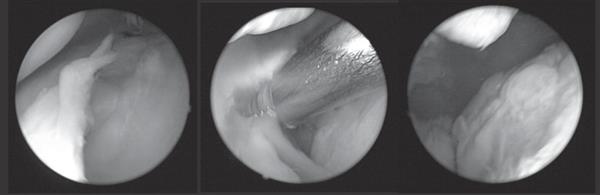

▲病變的滑膜組織充斥髕骨內側與股骨內側髁間隙;中圖,「關節鏡內側放鬆術」過程中將肥厚的內側皺襞和相關組織予以清創和清除;右圖,「隱藏病灶」清楚可見。

通常,「退化」性膝關節炎的關節間隙異常狹窄,很難透過常規關節鏡檢查發現隱藏在狹窄間隙內的病灶,只有在經過適當的滑膜切除及關節鏡「內側放鬆術」後,才會現出全貌(見上圖)。因此,「內側放鬆術」是解除「內側摩擦現象」的關鍵技術。